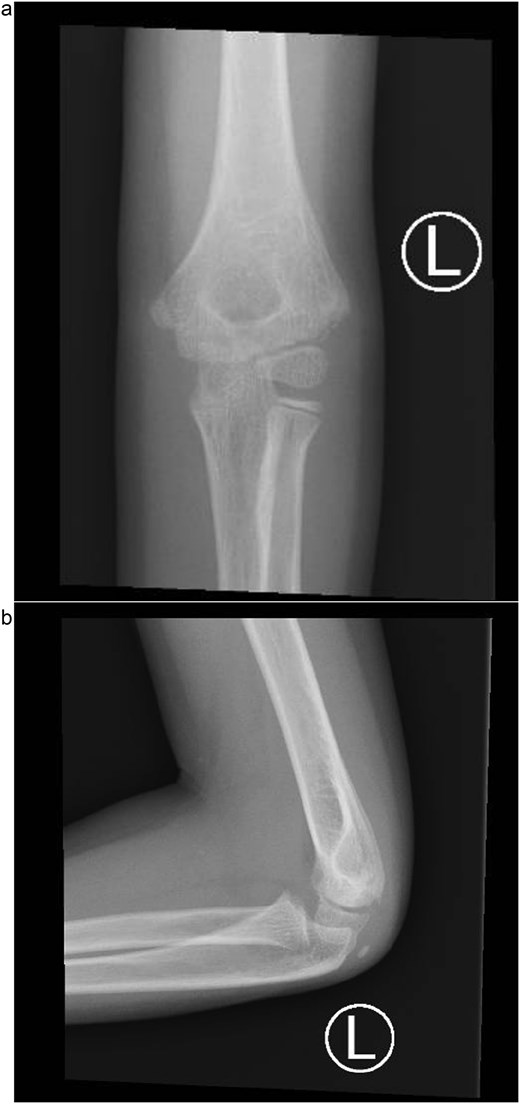

At the 3-week follow-up, dressing changes and radiographs showed satisfactory alignment and stable fixation. By 6 weeks, radiographs confirmed union of the lateral condyle, the Kirschner wires were removed, and mobilization began. At 3 months, the patient had painless motion from 10° to 120° with a stable joint. By 6 months, he achieved full range of motion and a normal carrying angle, with no radiographic signs of growth disturbance, avascular necrosis, or fishtail deformity (Fig. 5a).

(a) Six-month follow-up anteroposterior radiograph showing complete union of the lateral condyle fracture after Kirschner wire removal. (b) Six-month lateral radiograph demonstrating full healing with restored joint alignment, maintained carrying angle, and no evidence of growth disturbance or deformity.